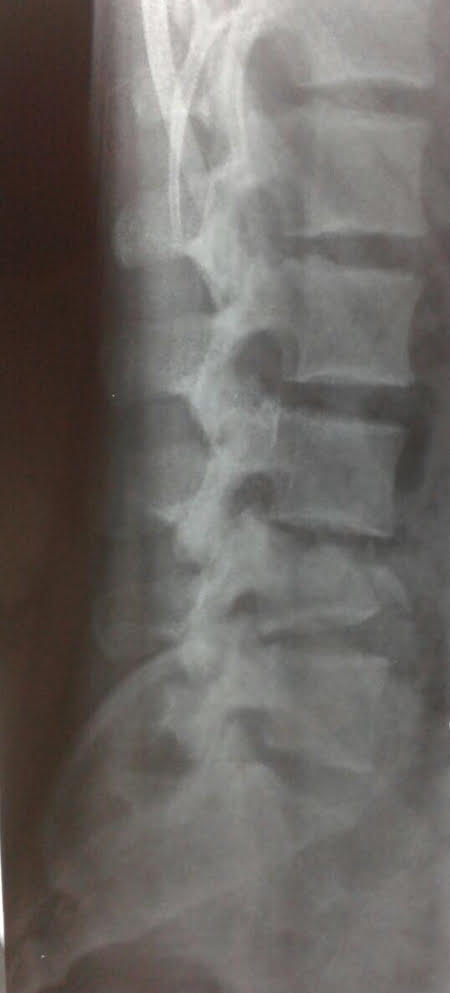

El paciente es trasladado al Servicio de Urgencia del hospital regional y, de allí, es derivado a nuestro centro, a través de su obra social. Ingresa, reactivo, lúcido (escala de Glasgow 15/15), con estabilidad hemodinámica y síndrome de cauda equina incompleto (grado B según el puntaje de la ASIA).19 Se solicitan radiografías y TC de columna cervical, torácica y lumbosacra. Se constata fractura vertebral lumbar baja con compromiso de la cuarta vértebra lumbar (L4), de tipo estallido, con retropulsión de un fragmento voluminoso del muro posterior en el canal, con impronta en el saco dural. La resonancia magnética no mostró una lesión del complejo ligamentario posterior, por lo que se interpreta, según la clasificación AO, como L4: A3, N3, M0 (Figuras 2 y 3). Sin deformidad en cifosis significativa y con un colapso vertebral inferior al 50%. Se constata una lesión hepática asociada, se lo somete a una laparotomía de urgencia y queda internado en la Unidad de Terapia Intensiva.

Figura 2.

Caso 1. Tomografía computarizada, corte axial.

Figura 3.

Caso 1. Tomografía computarizada, corte sagital.

Se decide efectuar una cirugía con abordaje posterior lumbosacro, descompresión posterolateral directa por técnica de tipo eggshell, con resección del arco posterior de L4 y reducción de los fragmentos en retropulsión.25-27 Se realiza artrodesis lumbosacra larga L2-S1 (Figuras 4 y 5).

Figura 4.

Caso 1. Control radiográfico posoperatorio (perfil).